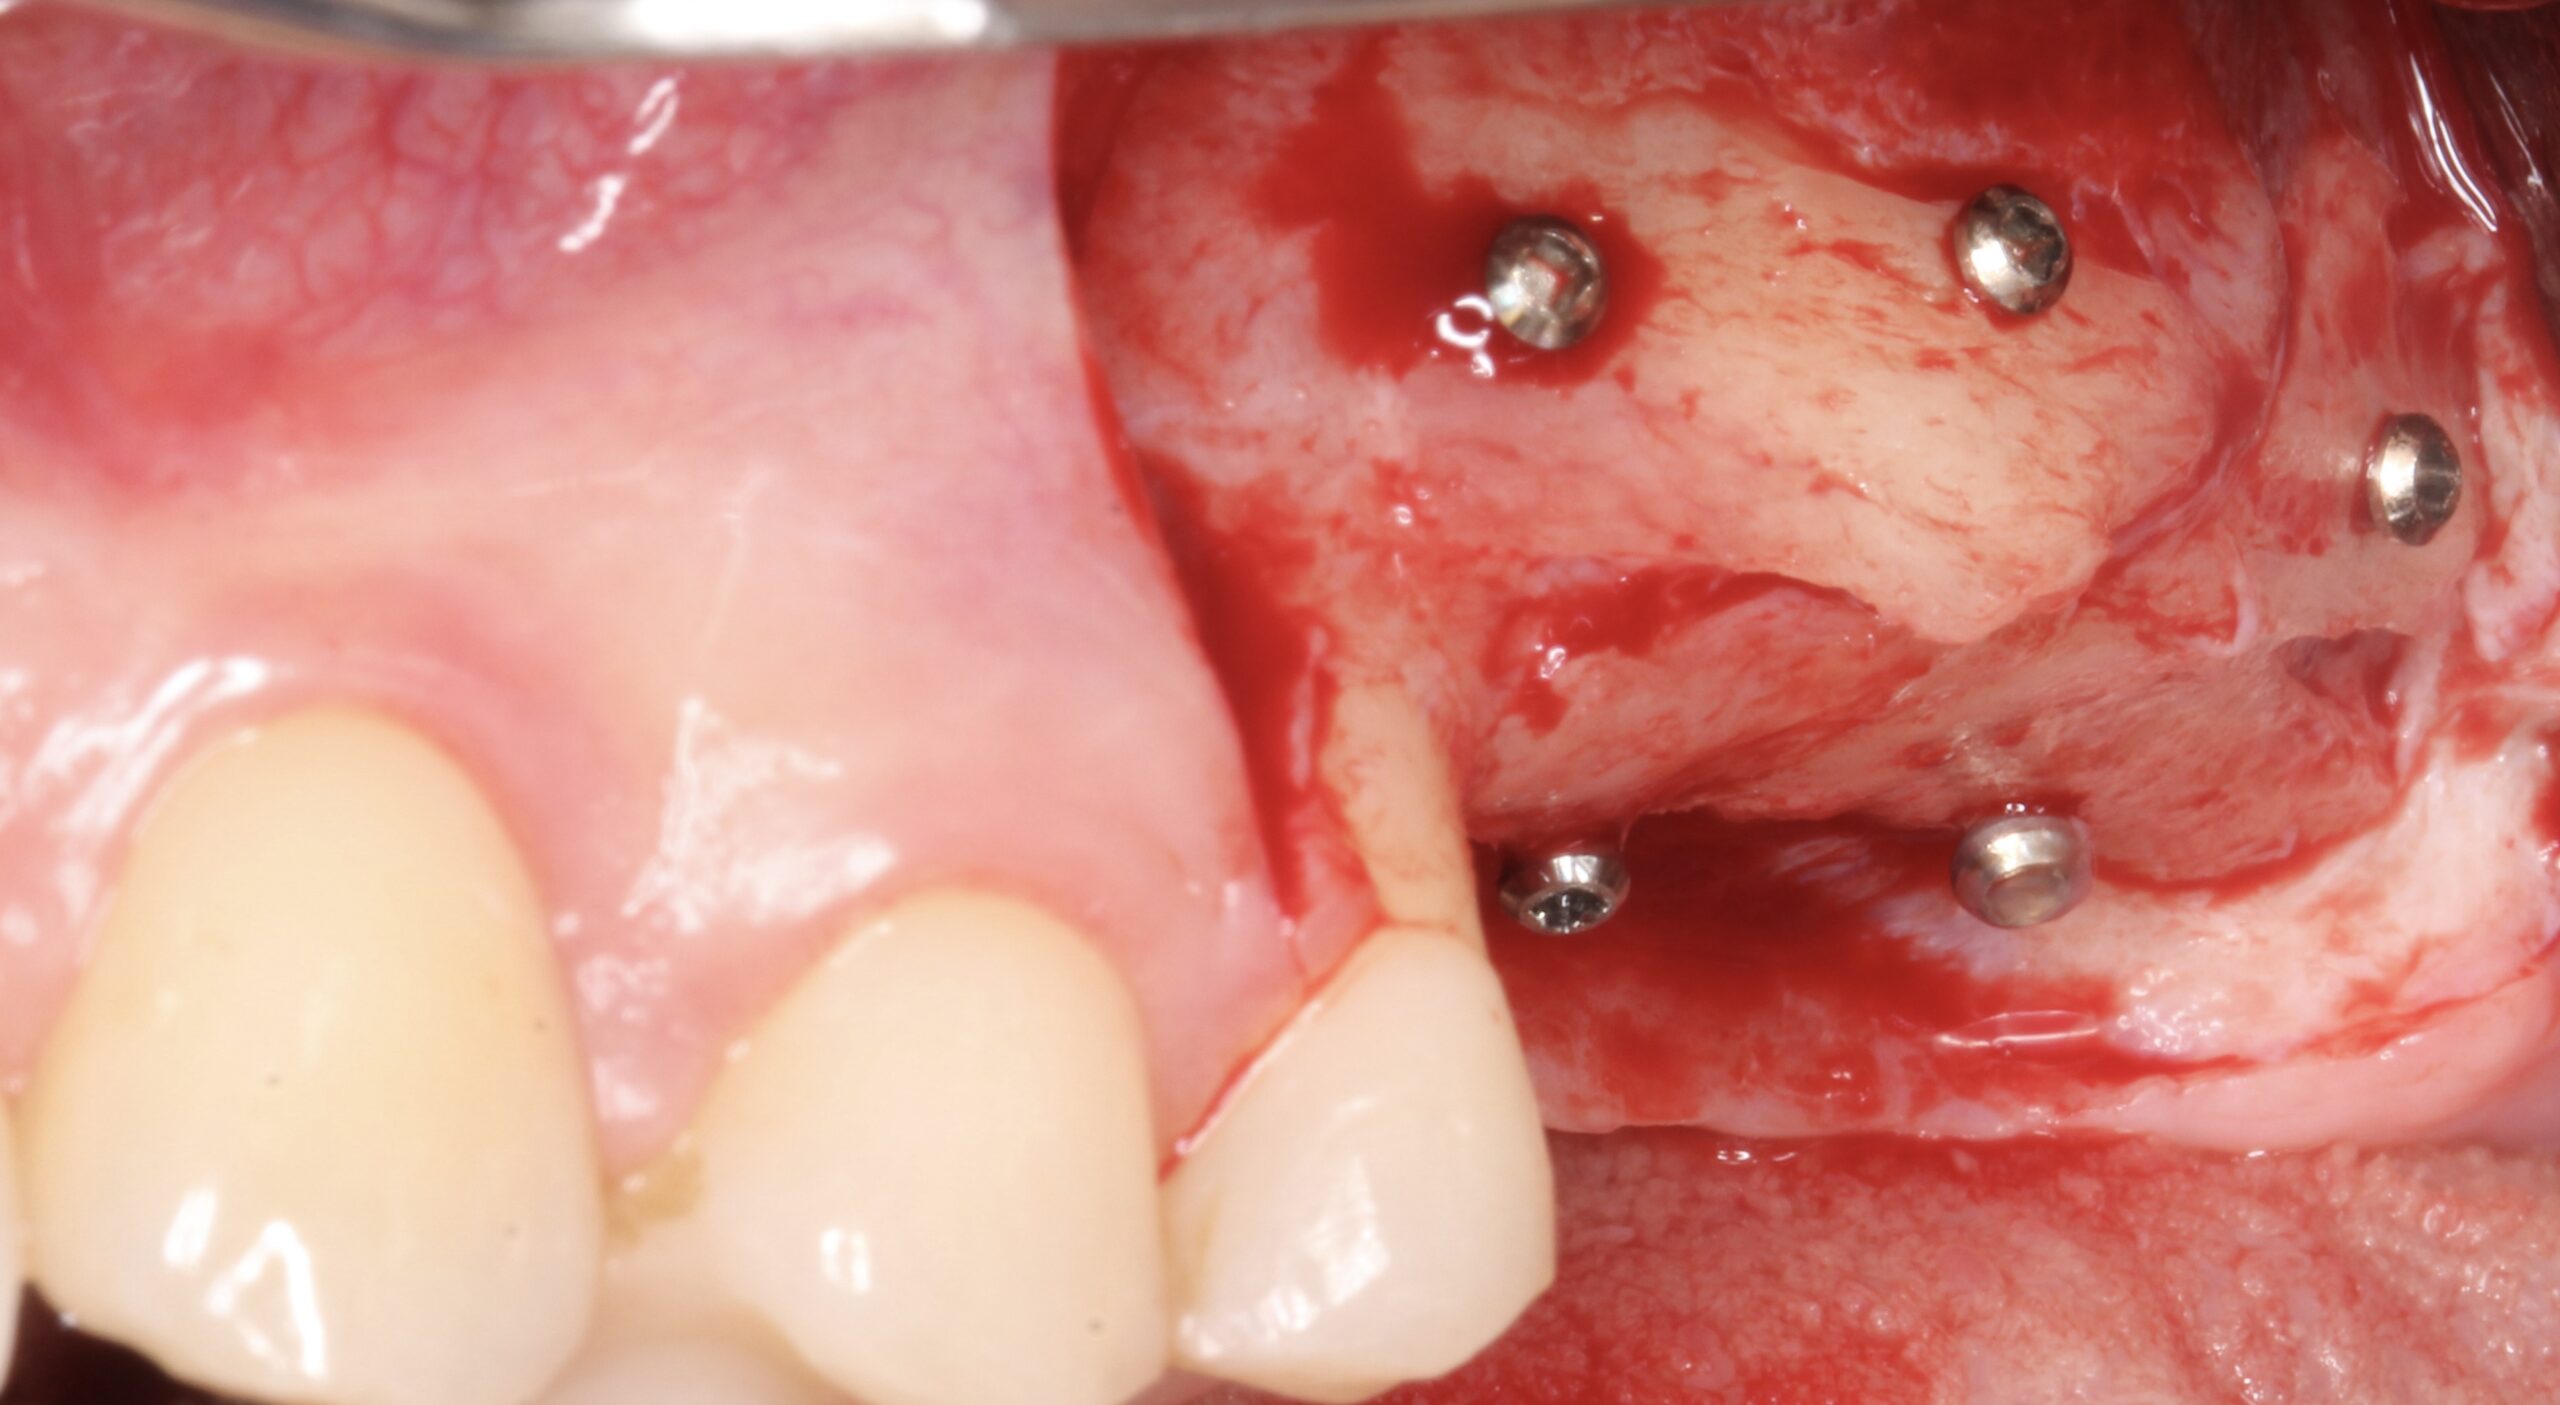

Figure 10.

After 4 months of healing reentry was carried out.

Figure 11.

Lateral view showing complete bone regeneration.

Figure 12.

Complete vertical bone regeneration